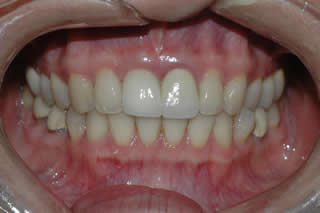

Front Single Tooth Implant:

Withou looking at the radiograph, can you tell which one is the implant tooth?